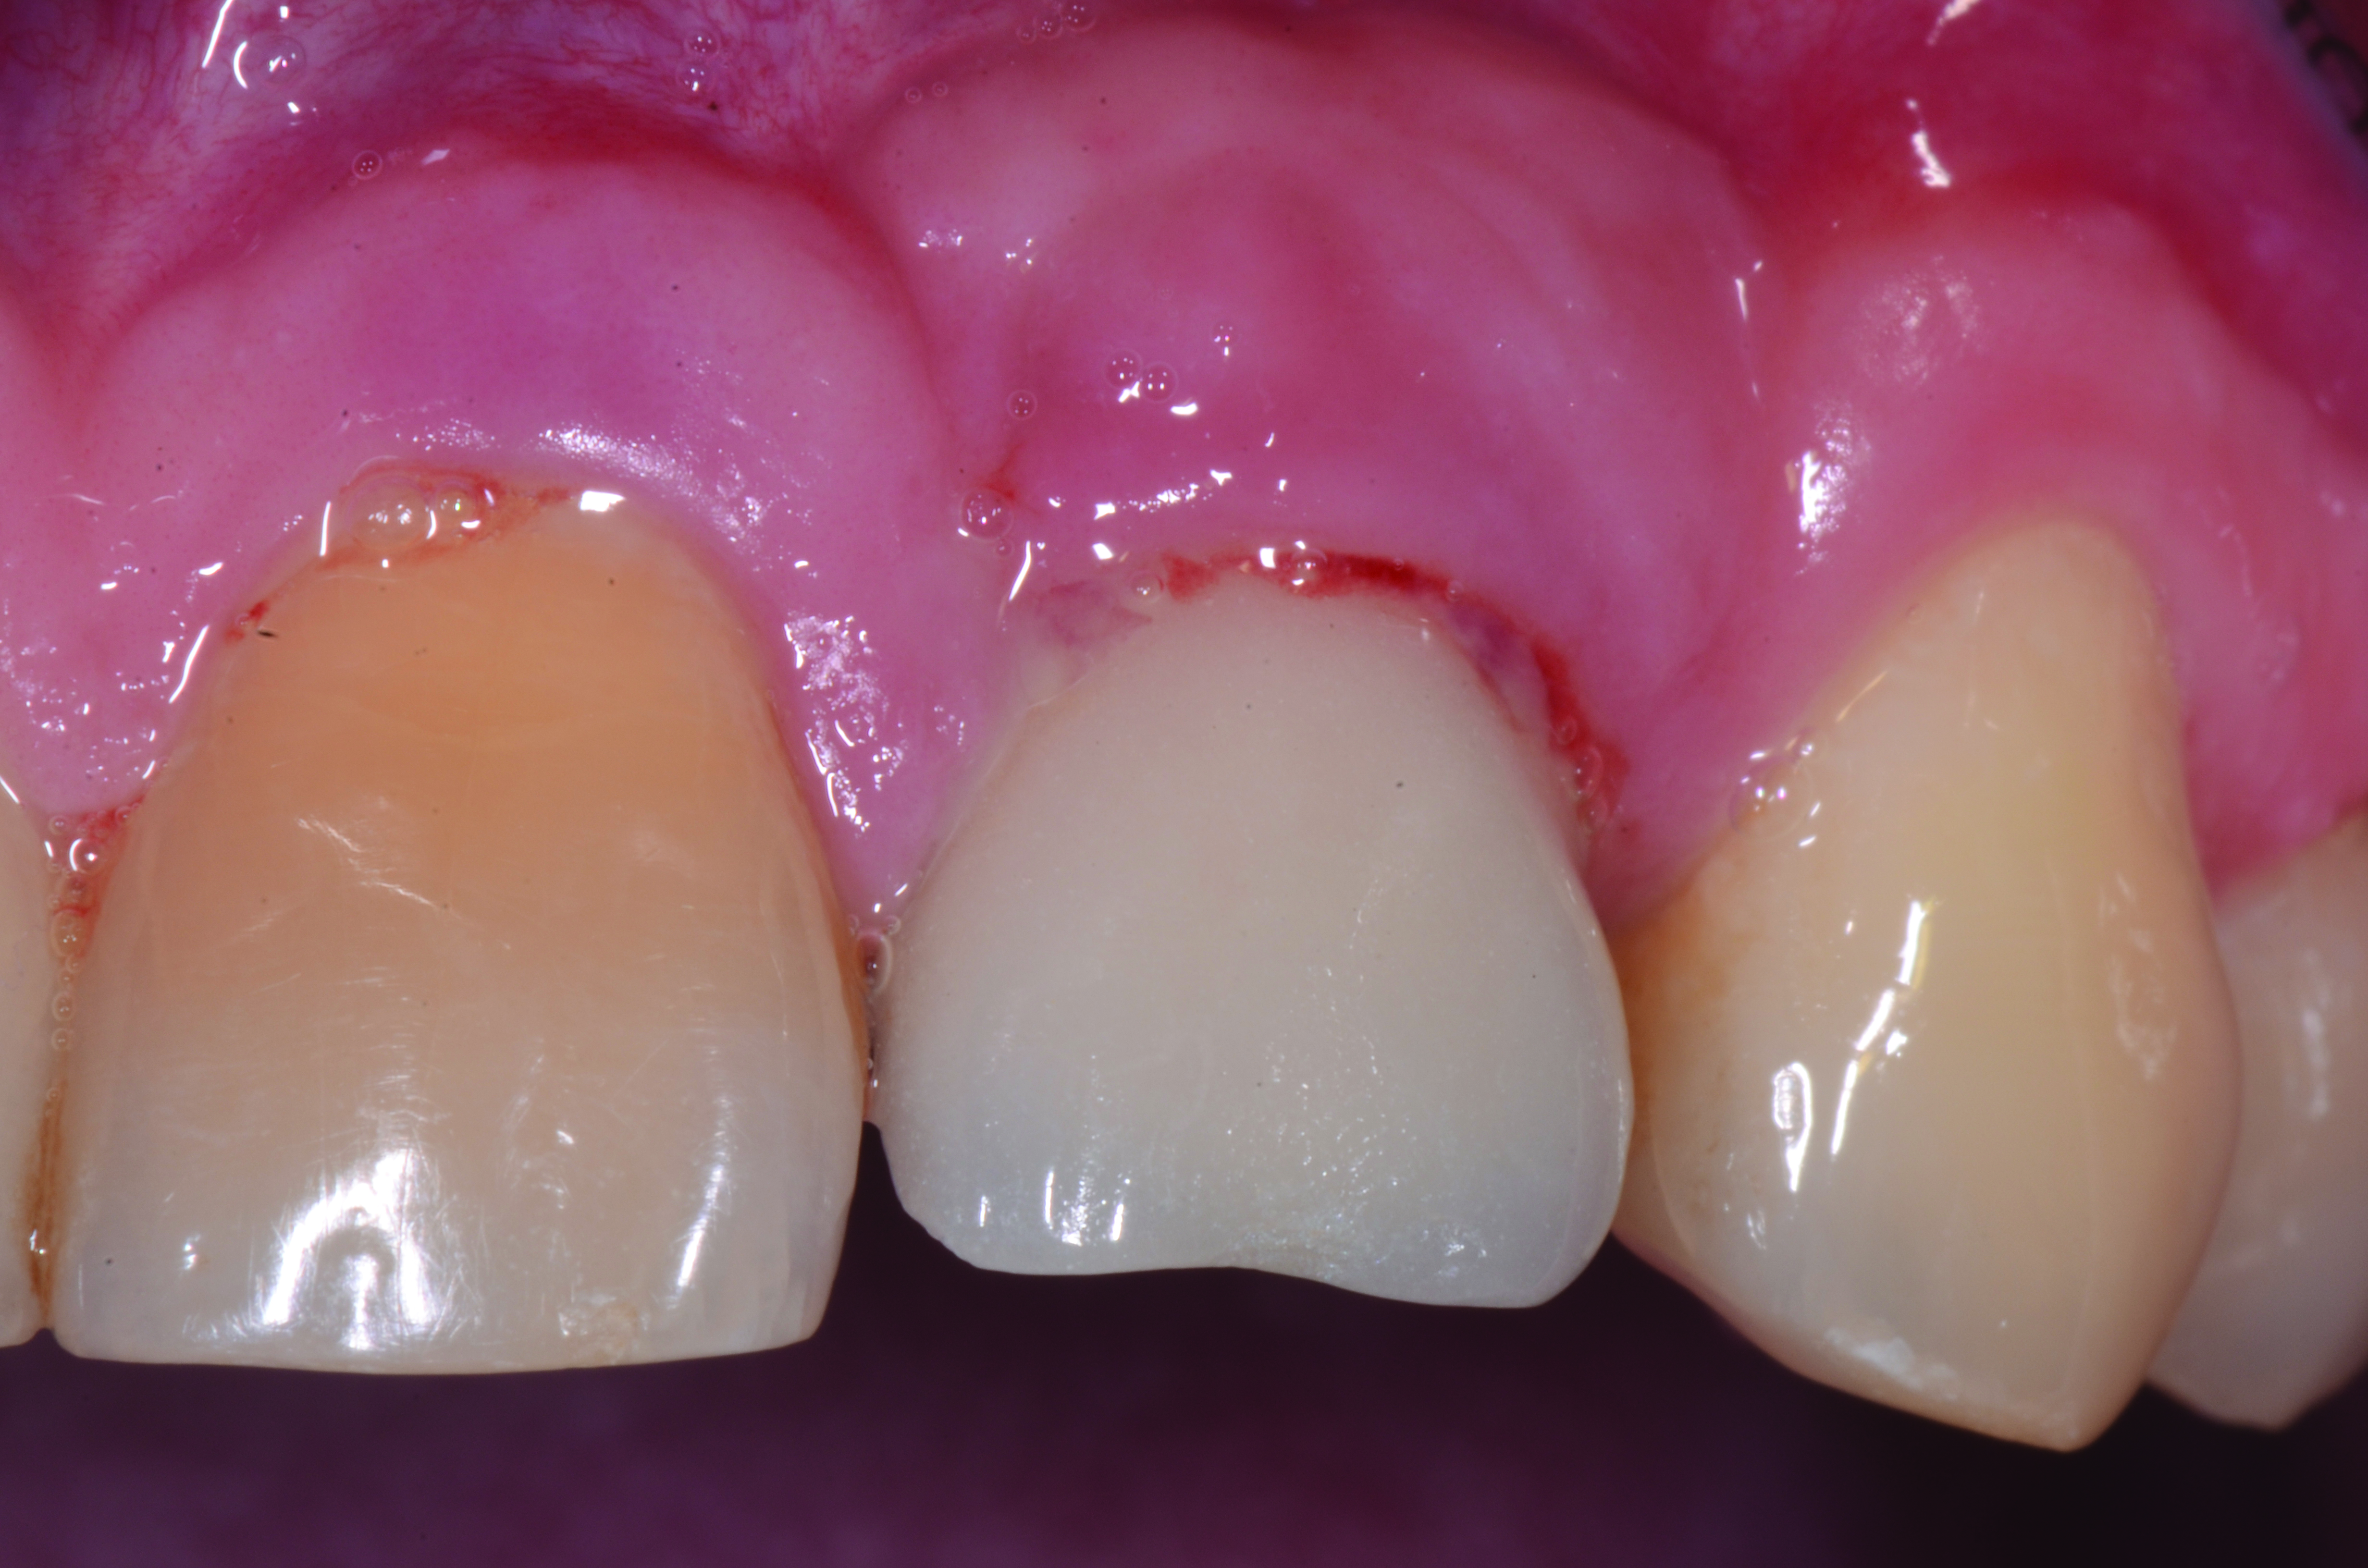

Peri-implant diseases present in two forms—peri-implant mucositis (Figure 1 and Figure 2) and peri-implantitis (Figure 3 and Figure 4). Both involve an inflammatory reaction in the tissues surrounding an implant—ie, bleeding on probing and/or suppuration; probing depths usually exceed 4 mm.1,3 However, when there is also bone loss present beyond the physiologic remodeling that may occur after implant placement, a diagnosis of peri-implantitis should be made, as this condition, when compared to mucositis, is far more serious and difficult to resolve.4

Clinical view of maxillary left lateral incisor implant in a healthy 48-year-old man. The swelling in the tissue surrounding this implant also bled on probing with depths up to 8 mm and exhibited purulence. The implant has been present for 14 years.

Figure 1

Radiograph of this same area. Note that there is no indication of bone loss and a long abutment collar. Hence, the diagnosis of peri-implant mucositis is given.

Figure 2